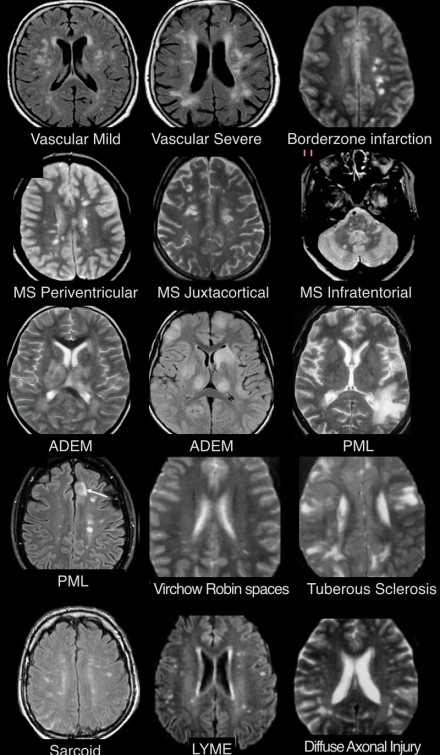

血管周圍間隙

圖片三:T2加權(quán)成像和FLAIR成像

請查看上圖并描述其病變特點。我們可以看到,在T2加權(quán)成像上,在基底節(jié)上有多個高密度病灶。在FLAIR成像上,這些病灶呈黑暗模糊影,在所有序列成像上,與腦脊液的密度相近(在T1加權(quán)成像上呈低信號)。

結(jié)合信號密度和病灶部位,可以判斷是典型的血管周圍間隙。

圖片四:FLAIR成像

血管周圍間隙是穿透軟腦膜血管周圍的腦脊液間隙。通常位于基底神經(jīng)節(jié)、腦室周圍、前連合附近以及腦干中間。在MR成像圖像上,在所有序列上的密度與腦脊液的密度相近。與其他白質(zhì)損傷病灶不同,血管周圍間隙在FLAIR和PD成像上呈黑暗模糊影,通常比較小,位于前連合附近的除外,此處的血管周圍間隙比較大。

在上圖中,我們可以看到比較寬的血管周圍間隙和在白質(zhì)中有融合的高密度信號病灶。該圖像很好的顯示了血管周圍間隙和白質(zhì)損傷病灶之間的差異。

由于周圍結(jié)構(gòu)組織的萎縮,血管周圍間隙會隨著衰老和高血壓而逐漸增寬。